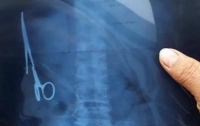

04:26 Здоровье

Мужчина проглотил ножницы и едва не умер